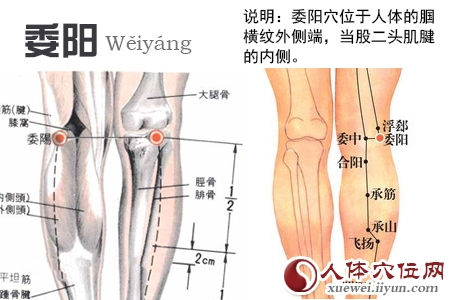

膝彎部膕橫紋外側端,股二頭肌腱內側緣凹陷處。

- 肌肉:外側為股二頭肌肌腱。深層為腓腸肌外側頭、膕肌起始腱、跖肌。

- 神經:股後皮神經、腓總神經。

- 血管:膝上外側動、靜脈。